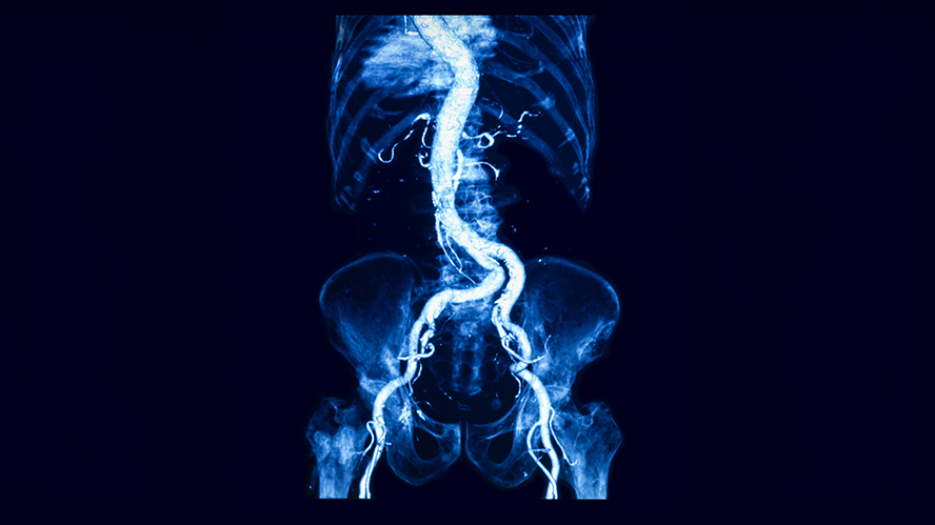

The aorta runs from the heart through the chest and abdomen. In the lower part of this main artery, a bulge—called an aneurysm—can rupture, causing life-threatening bleeding.

Although initially asymptomatic, AAAs are defined as a swelling of the abdominal aorta—the portion of the aorta that carries blood from the heart to the abdomen. Progressive weakening and dilatation (being stretched or widened) of the vessel wall make it more likely to rupture, which is a surgical emergency and results in death in 50% to 85% of patients. There is limited understanding of how AAAs form and how risk factors such as smoking and arterial plaque buildup contribute to clinical outcomes.